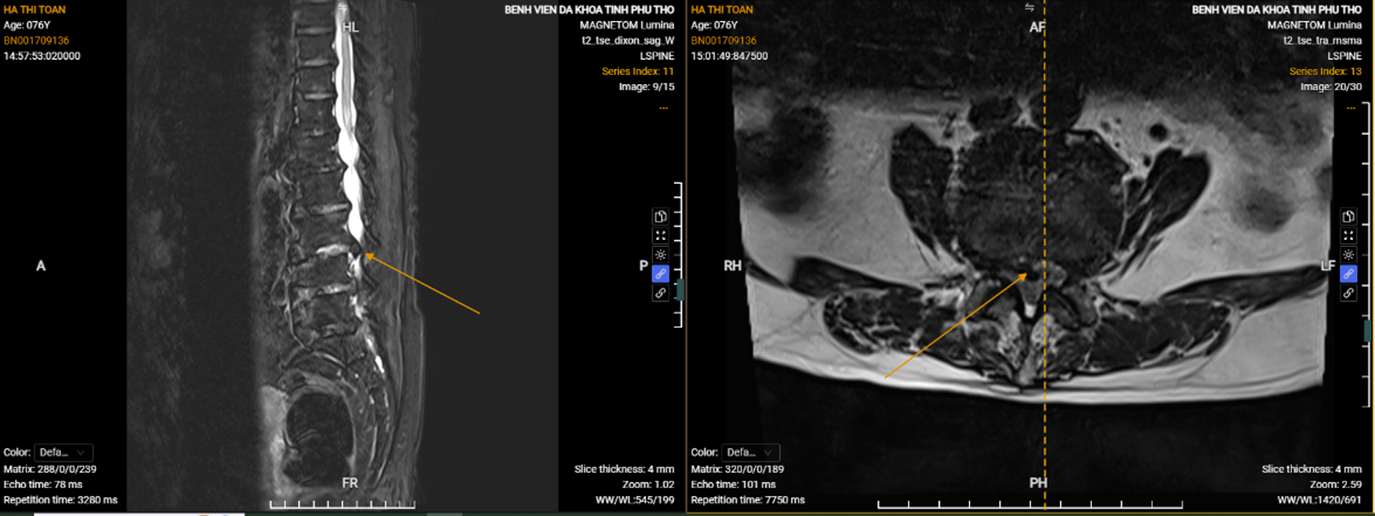

Hình ảnh phim chụp thể hiện vị trí thoát vị của người bệnh Hà Thị Toản.

Người bệnh bị thoát vị đĩa đệm tái phát sau khi điều trị tại một bệnh viện ở Hà Nội. Cơn đau có lúc khiến người bệnh không thể đi lại, phải nhờ người thân cõng. Lần này bệnh tái phát, gia đình quyết định đưa người bệnh đến Bệnh viện Đa khoa tỉnh Phú Thọ điều trị.